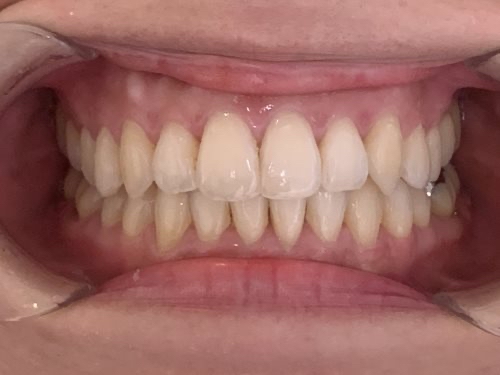

30代女性「ガタガタの前歯と口元の突出感が気になる」マウスピース型矯正装置「インビザラインフル」を使い、非抜歯で歯並びと噛み合わせを改善した症例

歯並びがきれいに整い、見た目と噛み合わせが改善しました。

患者様も「きれいになって嬉しい」と非常にご満足されており、笑顔も増えているご様子です。

現在は、後戻り防止装置の「リテーナー」を使用しながら、きれいな状態を維持するために定期的にご通院いただいています。